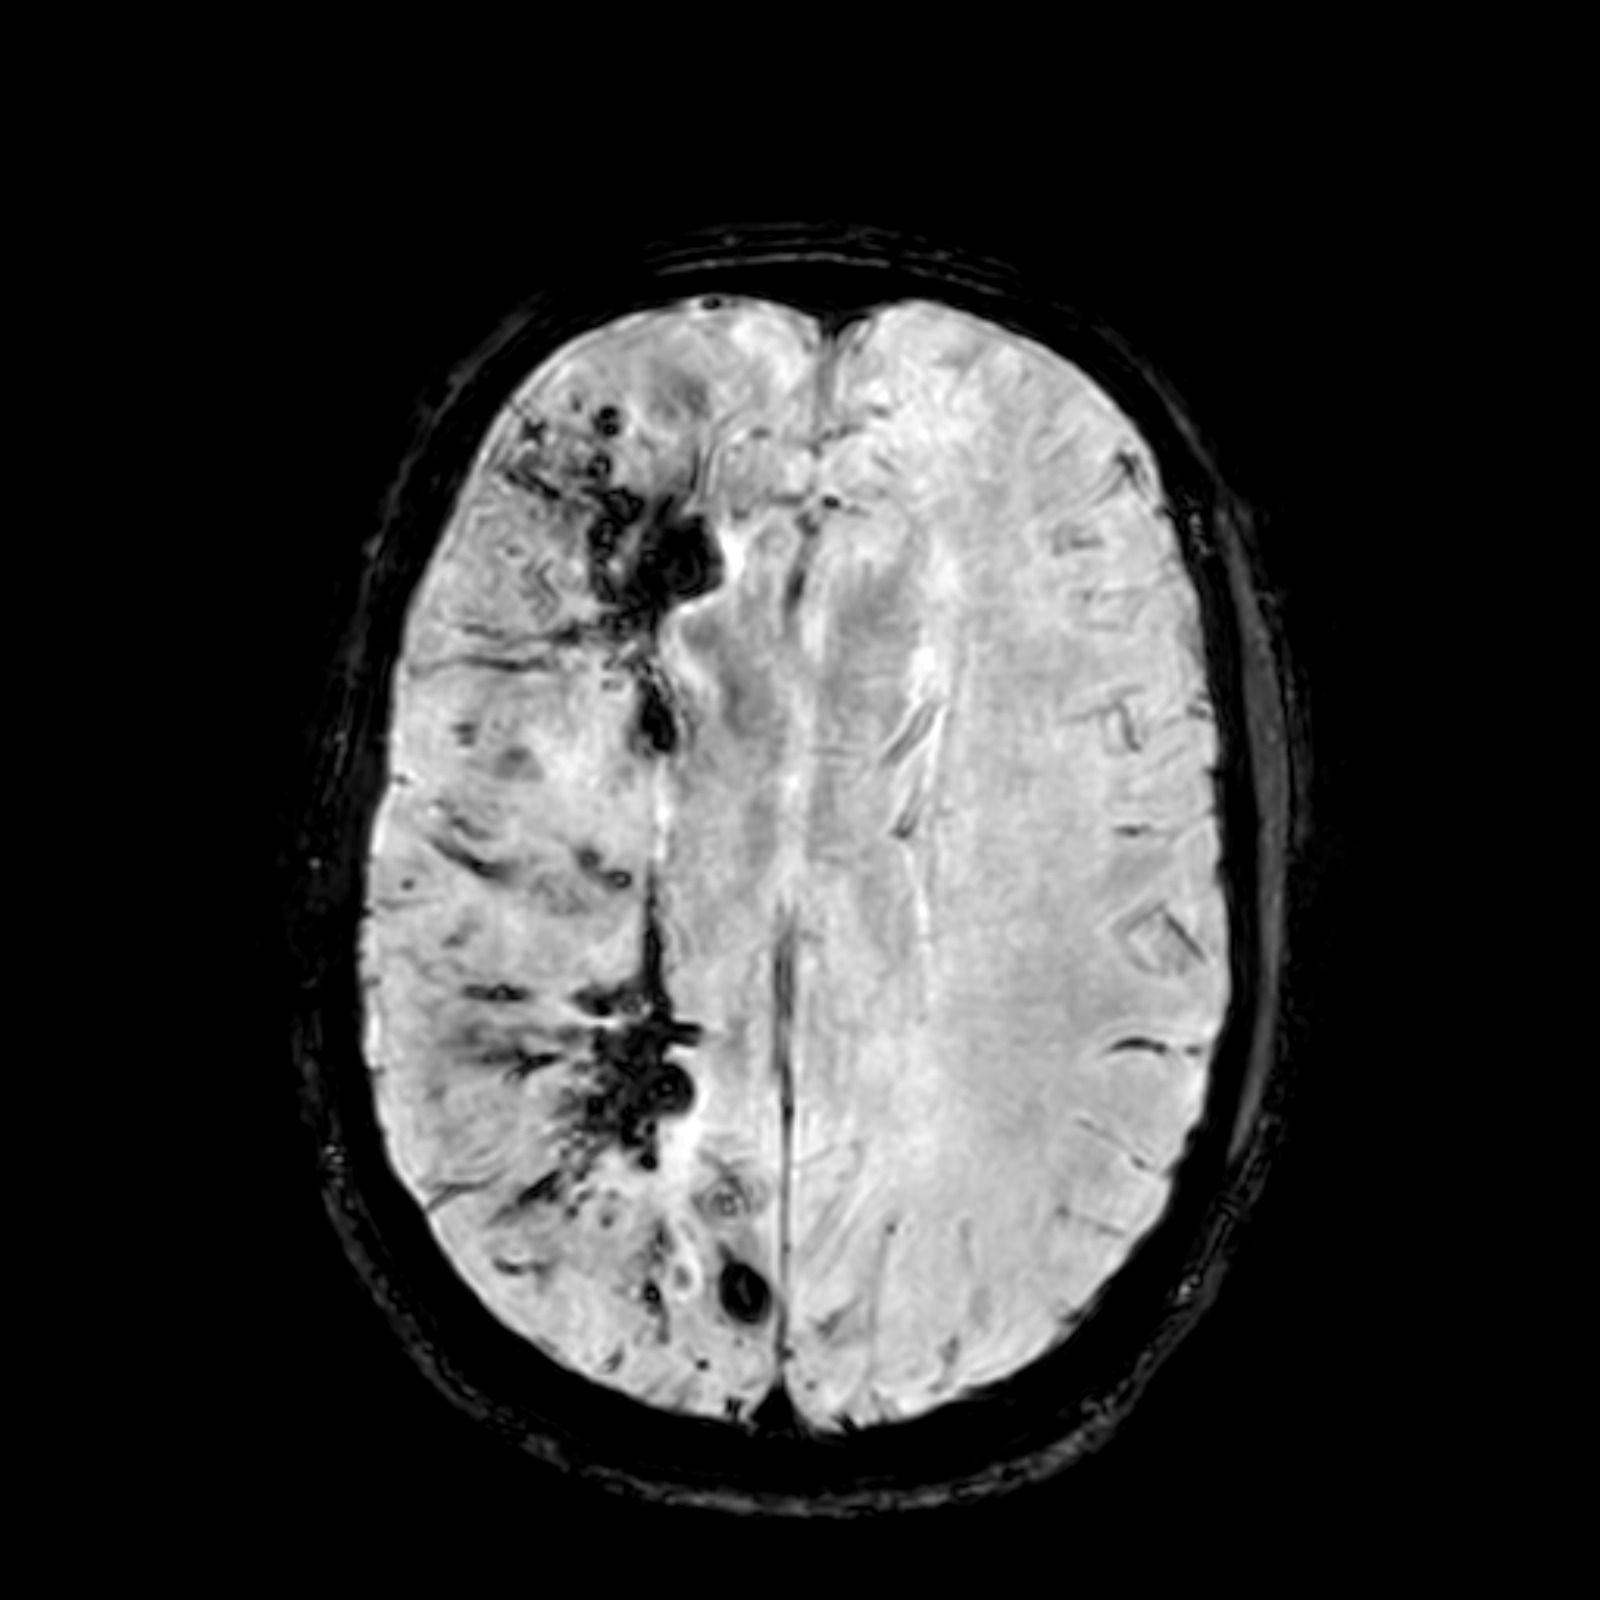

Overview of cerebral cavernous malformations: comparison of treatment approaches

This work presents the issue of treatment of cerebral cavernous malformations (CCMs) in terms of intervention and observation. A meta-analysis and systematic review were performed involving 98 primary publications with a total of 100 cohort studies yielding 8994 patients who underwent surgery, radiosurgery, or conservative treatment with the disease during 1990−2020. All this work was subject to precise methodological rules according to the official PRISMA (Preferred Reporting Items for Systematic Reviews and Meta-Analyses) documentation. The risk of bias in the analysed studies was assessed using Newcastle-Ottawa Scale (NOS). Exclusively studies with a high or medium risk of bias (≥ 6 * according to NOS) were included in the final statistical analysis. The main aim of the statistical processing was to (1) calculate overall haemorrhage rate, case fatality and long-term in each predefined treatment modality, (2) specify the treatment efficacy and mortality/morbidity rate by calculating the cumulative incidence with corresponding 95% confidence intervals (CIs) for each outcome using the random effects model, and (3) investigate further associations among patients’ demographics and posttreatment haemorrhage rate by calculating adjusted rate ratios with 95% CIs according to Poisson’s distribution models. Finally, sensitivity analyses of overall case fatality and haemorrhage rates were conducted in high-quality cohorts, i.e., those with prospective design or in which the outcome of interest was not present at the start of the study. The heterogeneity test was performed using Cochran’s Q and I2 statistics. All computations were performed with MetaXL and STATISTICA software.

The efficacy of ensuring the prevention of haemorrhage was 97% in surgical, 86% in radiosurgical and 77% in the conservative treatment. The lowest mortality (1%) was after radiosurgery, and the highest persistent morbidity (22%) was in natural history series. Deep-seated and brainstem CCMs were associated with higher bleeding rates. Lobar localisation was a protective factor in all analyses. Patients with history of previous haemorrhage were exposed to higher risk of rebleeding. Male gender was a protective factor associated with lower risk of post-treatment haemorrhage.